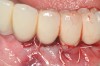

Dental implants have revolutionized the way in which clinicians treat and restore partially and fully edentulous patients and have demonstrated success for managing a broad range of clinical dilemmas. While implants have been highly predictable and have achieved long-term success, they are not immune from complications associated with improper treatment planning, poor surgical and prosthetic execution, material failure, and inadequate or infrequent maintenance. Among these problems are the biologic complications of peri-implant mucositis and peri-implantitis, which are inflammatory conditions in the soft and/or hard tissues surrounding dental implants (Figure 1 through Figure 4).1,2

Fig 4. Clinical view of the area 3 months post-therapy. Shallow probings of 3 mm were present around the dental implants with absence of bleeding. However, the mucogingival deformities remained on the premolar implants and would require treatment.

Figure 4